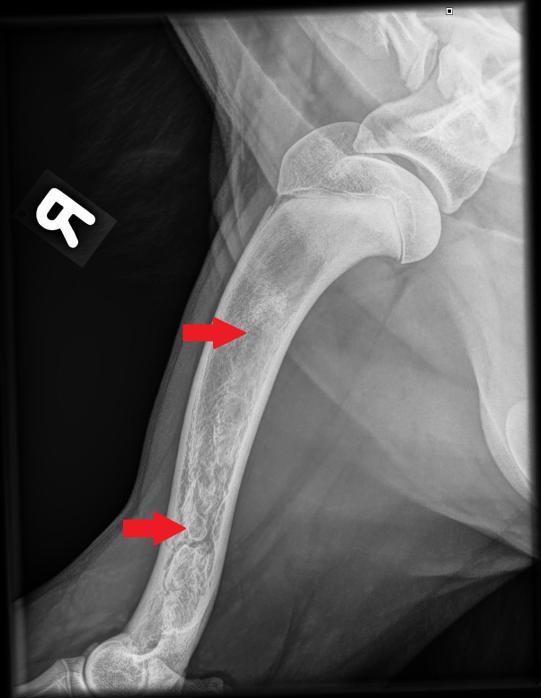

Beim Folgebesuch einige Tage später ist der Hund wieder ganz der alte - ungestüm, fröhlich und mit prächtigem Appetit gesegnet. In Sedation werden nun beide Vorderbeine geröntgt, um zu eruieren, was zu der wechselhaften Lahmheit geführt hatte.

Die typischerweise von Wachstumsstörungen betroffenen Gelenke (Ellbögen und Schultergelenke) erscheinen wie erhofft unauffällig. In sämtlichen Langknochen (Elle, Speiche, Oberarmknochen) beider Vorderbeine zeigen sich jedoch starke Veränderungen: Das Knocheninnere weist an verschiedenen Stellen fleckige Verdichtungen auf, welche die normale feine Knochenstruktur verdrängt haben. Die beobachteten Veränderungen sind typisch für eine sogenannte Panostitis. Die Besitzerin erhält einen Vorrat an Schmerzmitteln, falls das Problem wieder aufflammen sollte.